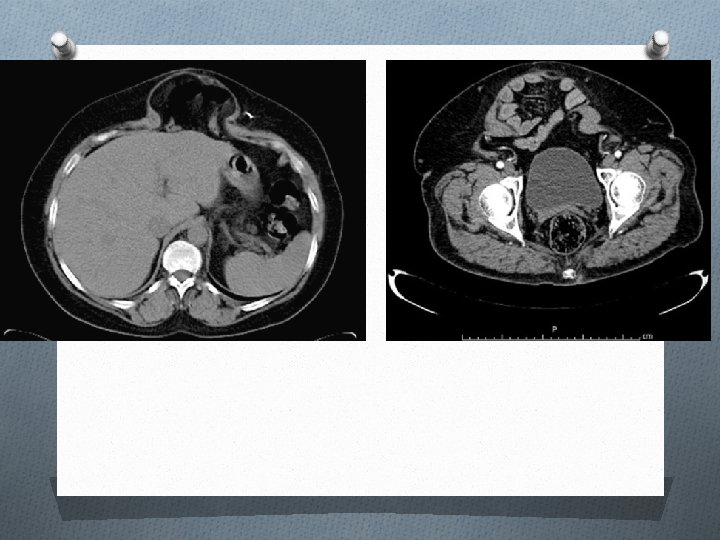

Tomografía

Ecografía abdominal. A nivel de la fosa ilíaca derecha se observa una masa de ecogenicidad homogénea, adyacente al borde de la pala ilíaca, y que parece tener un componente intraabdominal y otro componente en la pared abdominal. TC abdominal: masa sólida, de densidad tejidos blandos (similar al músculo adyacente, 44 UH), homogénea y bien delimitada. Tiene una morfología en reloj de arena, con un componente intraabdominal y otro en pared abdominal.